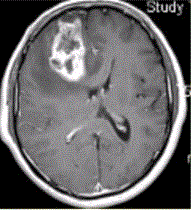

问题 患者女,67岁,头痛伴呕吐1周。既往体健。MR表现如下图。 关于多形性成胶质细胞瘤,描述正确的是

选项 A.儿童青少年常见 B.好发于额、颞叶大脑灰质及白质区 C.CT平扫密度均匀 D.增强检查均匀强化 E.瘤周水肿轻微,占位效应显著

答案 B